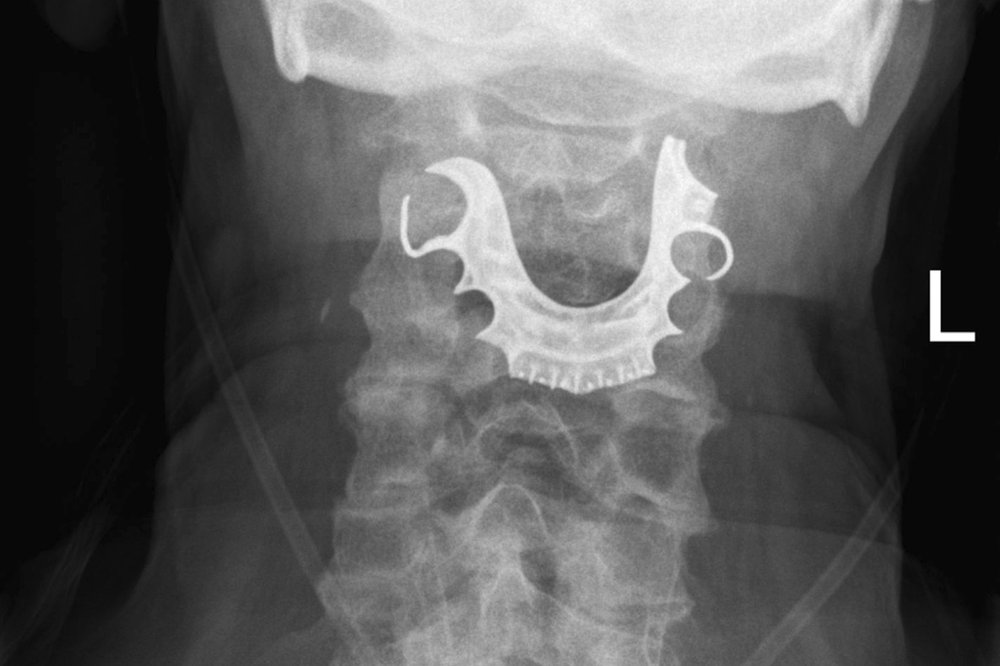

This undated X-ray image provided by the BMJ in August 2019 shows dentures stuck in the throat of a 72-year-old patient. They became lodged in his throat during surgery and weren’t discovered until eight days later. (BMJ via AP)

The man went to the emergency room because he was having a hard time swallowing and was coughing up blood. Doctors ordered a chest X-ray, diagnosed him with pneumonia and sent him home with antibiotics and steroids. It took another hospital visit before another X-ray revealed the problem: His dentures — a metal roof plate and three false teeth — lodged at the top of this throat.